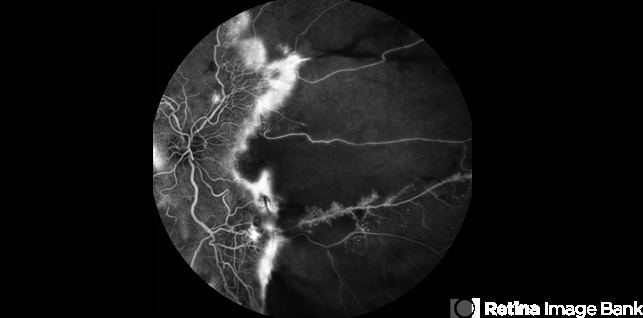

- proliferative retinopathy

- Fluorescein Angiogram on a 43 Year Old female with Proliferative Retinopathy.